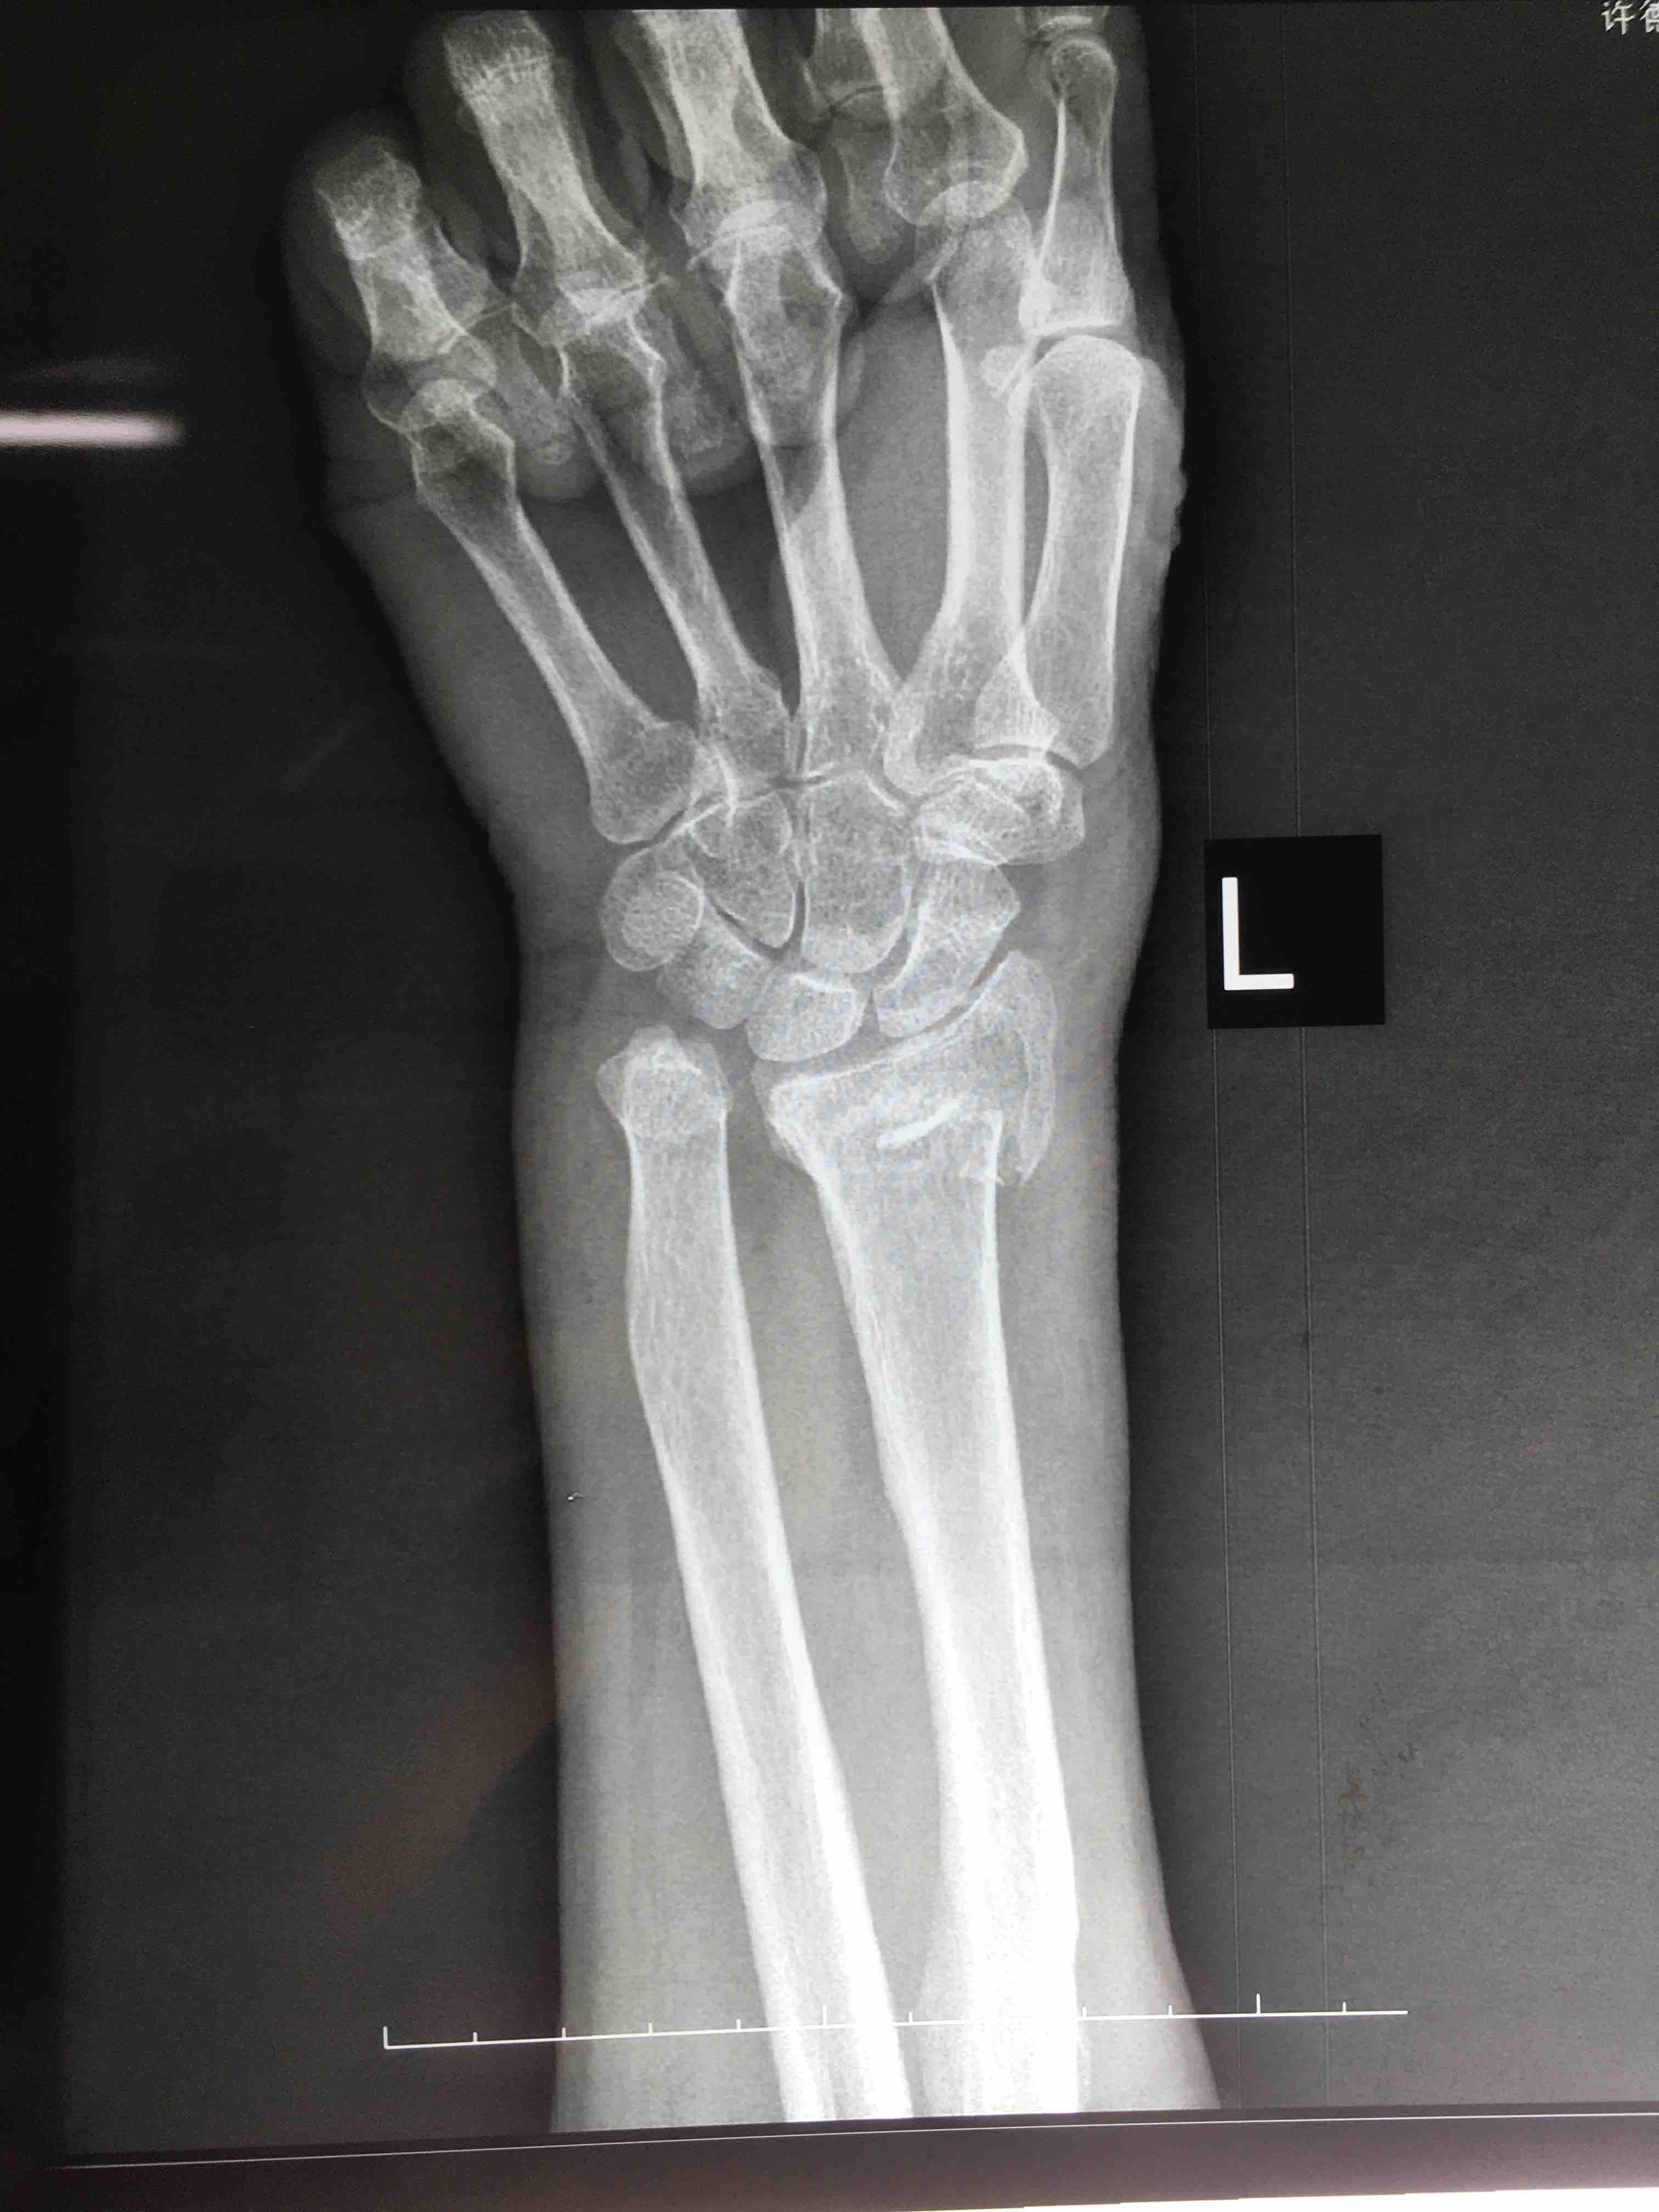

打开应用老年患者colles骨折(切复内固定术)

患者:女/七十四岁

摔伤后左肿痛,活动受限1小时入院。

左腕部肿胀明显,畸形,局部压痛及纵向叩痛阳性,活动受限,末梢血运感觉正常。

诊断 治疗

在臂丛麻醉下行切复内固定术,术后抗炎对症处理。